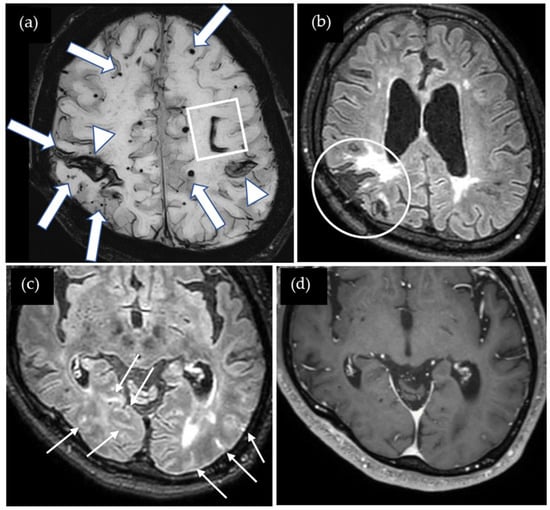

A 38-year-old man was found collapsed on the stairs and subsequently admitted to our hospital. On admission, right upper and lower extremity paresis was noted. He underwent left parietal craniotomy for a traumatic head injury at the age of six months. Cadaveric dura mater use was not confirmed. He had no history of hypertension or familial CAA. CT showed a lobar ICH in the left parietal lobe, and SWI showed multiple cortical CMBs adjacent to the ICH (Figure 2). The CAA-SVD score was 2 based on the previous literature [5], consisting of two points for lobar CMBs, zero points for cSS, zero points for CSO-PVSs, and zero points for WMH. Neither CSF examination nor amyloid PET was performed. Thus, this case was considered a possible iCAA based on the criteria [1].

Figure 2.

SWI shows multiple CMBs (arrows) adjacent to the lobar hemorrhage in the left parietal lobe (square).